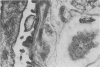

Rabbits given acute serum sickness (ASS) and treated with cyclosporin A (CyA) developed glomerular capillary thrombosis and cortical infarction, lesions not seen in unmodified ASS. Thirty-three NZW rabbits received a single intravenous injection of 250 mg/kg bovine serum albumen (BSA) with or without endotoxin (5 micrograms/kg) on day 0. Groups of rabbits were given intramuscular CyA as follows: 15 mg/kg from day -2 to +8, or 25 mg/kg/day from day -20 to +3 or day 0 to 5. Signs of this renal injury were haematuria, transient proteinuria, glycosuria and oliguria and they occurred during the rapid phase of antigen elimination when immune complexes were being formed. Seventeen of the 33 rabbits developed glomerular capillary thrombi and 11 of 17 also had glomerular and tubular infarction. Electron microscopic examination showed that these lesions were associated with severe endothelial injury and platelet-fibrin-leucocyte thrombi. These changes were more severe in the groups given 25 mg/kg. The lesions were not seen in untreated rabbits and ASS, nor in normal rabbits given equivalent doses of CyA alone. A strikingly similar renal lesion has been seen in patients receiving CyA following bone marrow transplantation, and also in the haemolytic uraemic syndrome. The model we describe may be valuable for the study of the mechanisms of endothelial injury and thrombosis in the kidney.